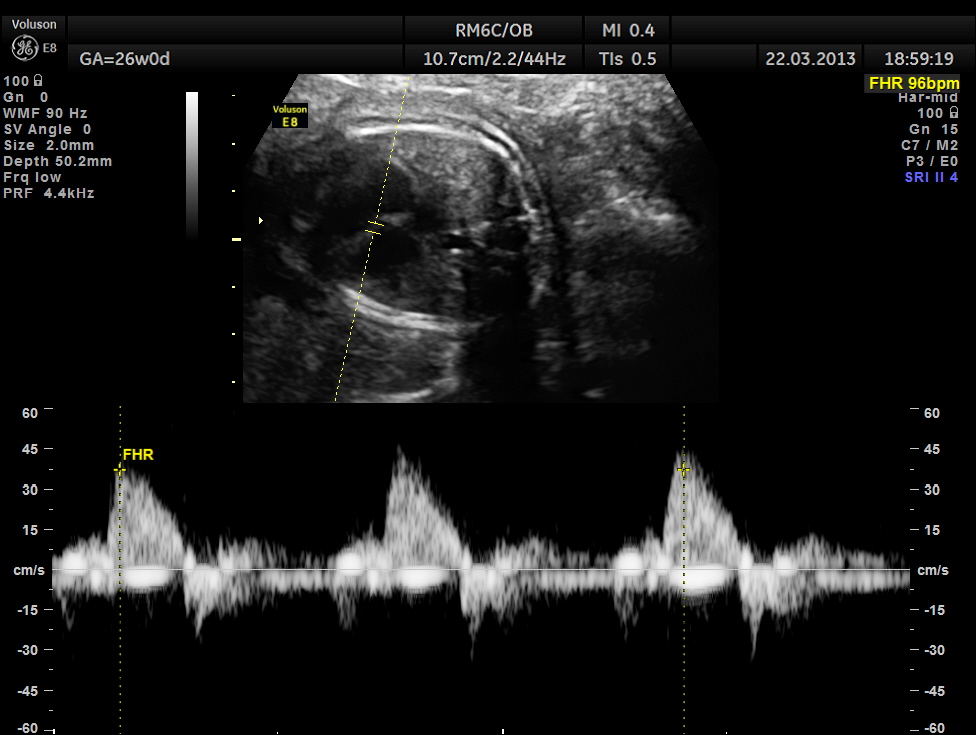

the following picture shows A.V.DISSOCIATION ( ventricular beats above and atrial below)

ventricular rate( above mid line ) is 96 bpm ;

atrial rhythm ( seen below base line ) shows dissociation